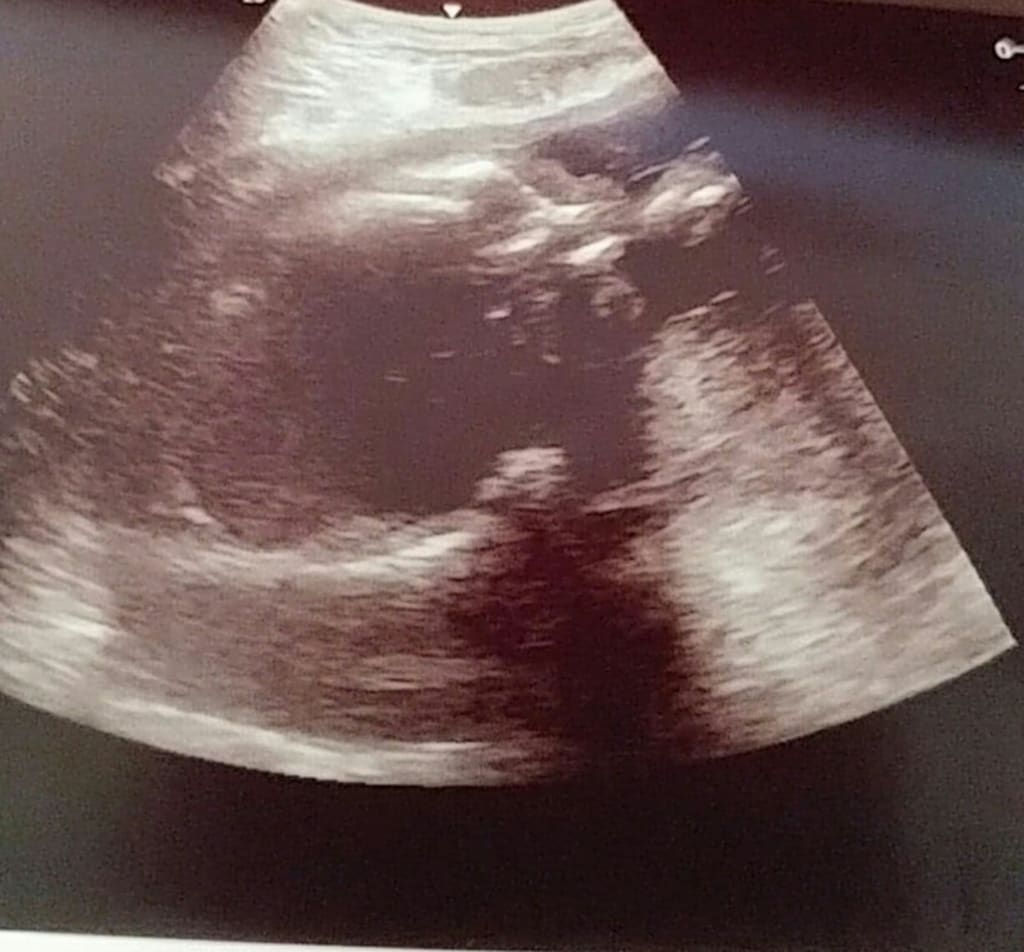

But knowing that the option of abortion was off the table also made me feel bad too, because it meant that, even if my boyfriend was both happy and panicked about the situation, it meant that he was stuck with me, and this child. And that was not something I had ever wanted. I wanted him to stay with me because he chose to and not because he had a responsibility to because of a baby. Even so, I still couldn't kill my baby. So the next step for me was going to the doctor, to be able to go and get an ultrasound and find out as much as we could about what to expect. As if all the stress we were already under wasn't enough, in between the time of my appointment with my general doctor, and the ob gyn he referred me to, my roommate/landlord had a meltdown due to going off his meds and having an explosive temper as it was, and I suddenly had to move back in with my parents as he lost his temper and assaulted me and I had no time to find another safe place to go. Time passed as we waited for the appointment day, and things continued to progress. Soon, I could not only feel the kicks, but SEE them too. It was another weird thing to get used to. But it was something I could share with my boyfriend even long distance. As the big day approached, we were a mess of emotions. Anxious, nervous, excited, and scared. What would they tell us? How far along was I exactly? How long did we have to prepare? Was the baby okay after me having no idea about the pregnancy for as long as I did? We'd guessed I was about 16 weeks along at the time at least, based on my symptoms and the dates I had visited him. And soon, the day arrived. Let me tell you, that for me, even as a trans man, the first time seeing my baby and hearing the little heartbeat was absolutely incredible. And the revelation that she was in fact, a little girl, and from all appearances, completely healthy! But then the next bombshell was dropped. I was at LEAST 23-24 weeks along. 5 months. A full month at least more than I had estimated. Which meant we had even less time to prepare, and that even if emotionally it had still been an option, abortion was completely off the table. And that was another big adjustment that we suddenly had to get used to. We had/have little to no time to prepare, and I knew I needed to move states before I was unable to fly, because I know I will need my boyfriend's support in order to get through this, and also because it is his child, and there is no way I am going to make him miss the moment she is born. He wants to be there too.